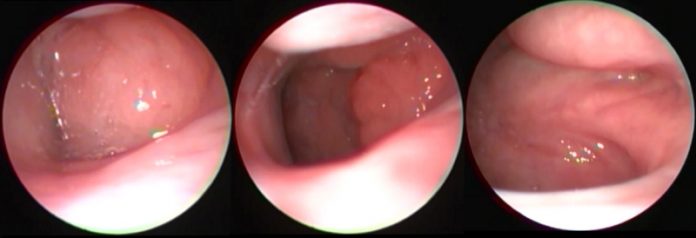

Op. Dr. Atilla Şengör geniz eti muayenesini uygulamalı olarak antatıyor.

İnce çocuk endoskopları ile burun ve geniz boşluğunu doğrudan görebiliyoruz. Bu sayede röntgen gibi radyolojik bir yönteme gereksinim duymuyoruz.Geniz etinin boyutunu, etkilerini anında görerek, gerekli tedavi planını yapabiliyoruz.